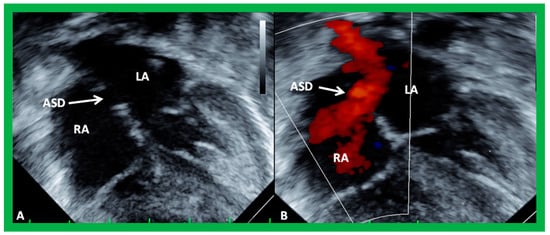

2. Diagnosis